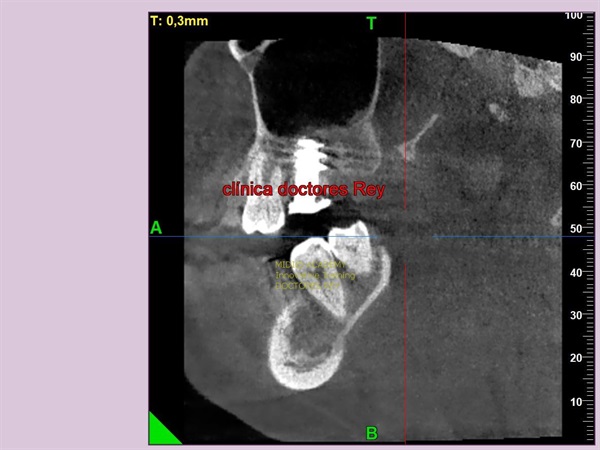

2-Implantes monobloque, en maxilar inferior. MIDI® TECHNIQUE® -US.

4x11,5. colocados con técnica ultarasónica MIDI®, hueso de calidad baja.

1- Implante de 9 mm de diámetro en maxilar superior post extracción + PRF. MIDI® TECHNIQUE®, no drill.

IMPLANTE EN MAXILAR SUPERIOR post extracción de diametro amplio 9 mm.

1- Implante de 9 mm de diámetro en maxilar superior post extracción + PRF. MIDI ®TECHNIQUE®, no drill.